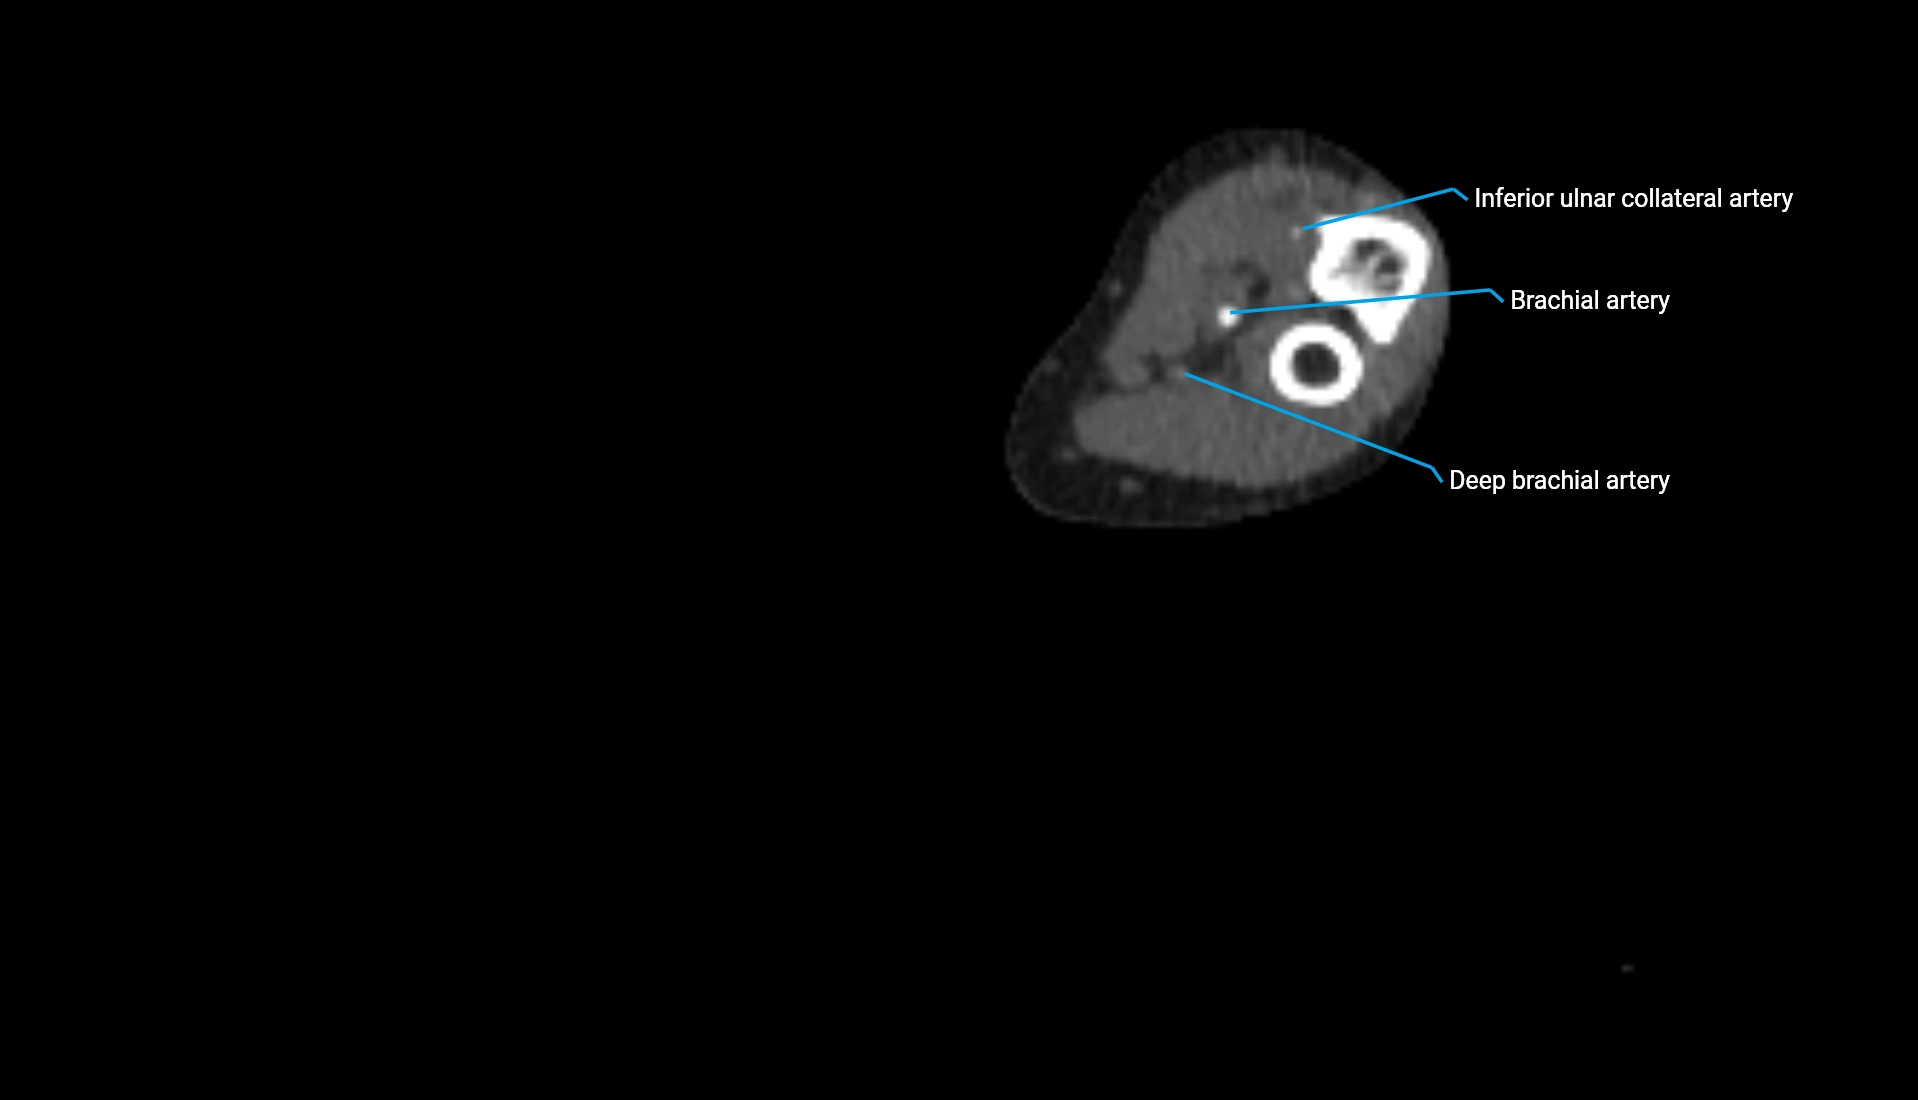

CT Appearance

Non-Contrast CT:

• Cortex: High-density, sharply defined

• Subchondral bone: Dense cancellous matrix

• Articular surface: Smooth concave contour articulating with the capitellum

• Excellent for evaluating bone integrity, alignment, and subtle fractures

Post-Contrast CT:

• Bone: No enhancement

• Joint capsule and synovium: Mild enhancement outlining the joint

• Improves contrast between soft tissues and bony margins

• Useful in detecting subtle joint abnormalities or postoperative changes